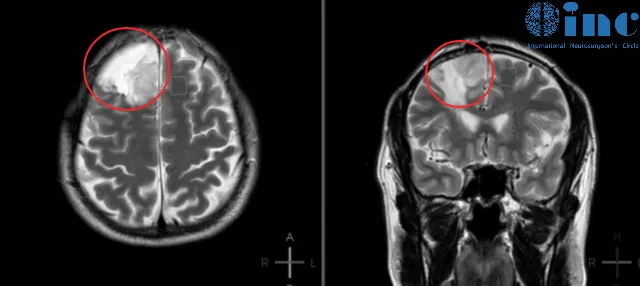

处于事业上升期的中年顾先生对健康问题高度重视。2014年因轻度面瘫就诊,影像学检查发现右额叶皮层区椭圆形肿块(尺寸约4.9cm×3.9cm×6.8cm),提示右侧额叶少突胶质细胞瘤可能。

确诊后不足一月,患者即在当地医院完成开颅手术。术后病理证实为右额少突胶质细胞瘤,WHO II级。术后每月服用替莫唑胺与丙戊酸钠片,持续六个月疗程。患者曾认为已成功摆脱脑肿瘤,但术后四年时(2018年)MRI复查提示复发可能。